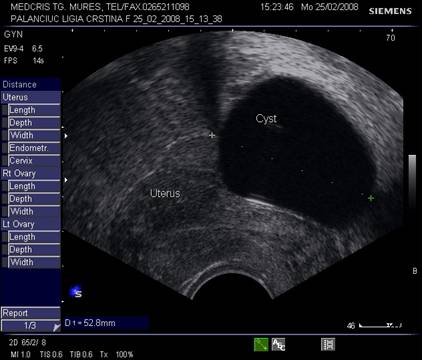

Fig. nr.388. Chist ovarian anecogen , unilocular , cu perete subtire la ecografia transvaginala